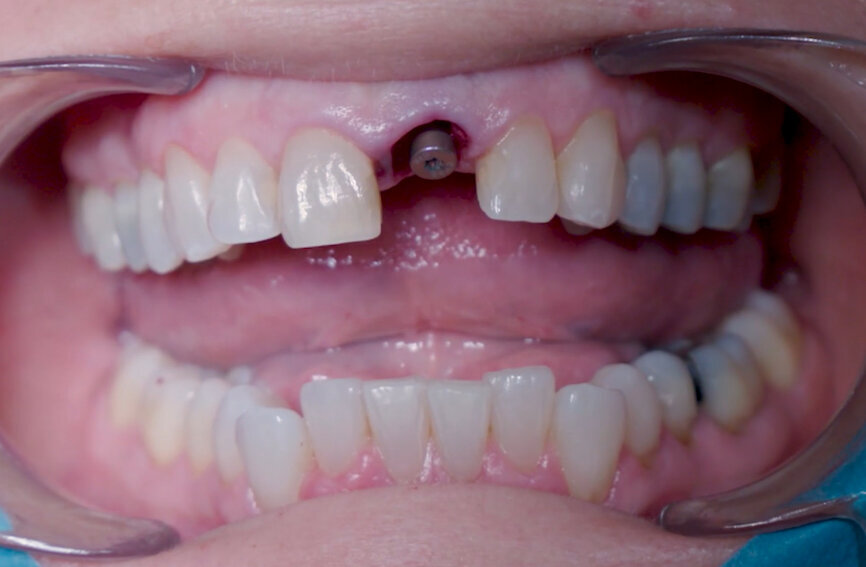

Fig. 27: Temporary crown seated and polished.

Fig. 28: Temporary crown one week post-op.

A Ø 4 mm temporary abutment with a gingival height of 2.5 mm was placed on to the implant, and it showed no crestal bone interference, allowing for appropriate creation of the emergence profile (Fig. 19). The tooth shell, which was designed and milled in PMMA prior to the procedure (Figs. 20 & 21), was tested to ensure that the contours and retention wings were appropriate and caused no interference (Figs. 22 & 23). The palatal side, including a small portion of the incisal edge, was opened in order to allow screw channel access (Figs. 24 & 25). The lateral wings of the tooth shell allow the provisional temporary crown to stay immobile during the pick-up procedure, which is a common problem clinicians face when performing the immediate pick-up technique. The tooth shell was bonded to the temporary abutment using flowable light-polymerising composite, and a slim emergence profile was created to the subgingival portion using the same material (Fig. 26). At this point, the retention wings were removed. With no compression to the soft tissue, the provisional crown was seated and the incisal edge adjusted to ensure that the antagonist tooth was not touching it in excursive movements. The provisional crown was torqued to 25 Ncm, and the screw access hole properly closed and polished (Fig. 27). The patient was seen seven days later for postoperative and periapical radiographic control (Figs. 28 & 29).